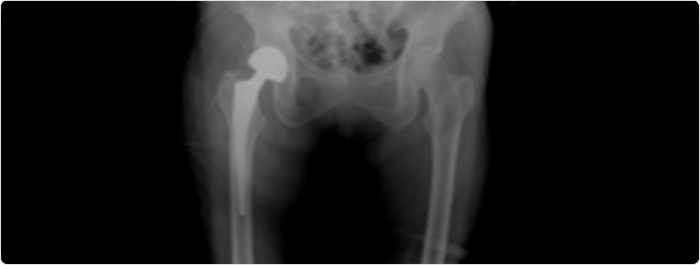

ดังนั้น จึงเป็นข้อบ่งชี้ทางการแพทย์ที่จะต้องทำการรักษา เพื่อให้ผู้ป่วยนั่งได้ พลิกตัวได้ จะได้ไม่เกิดโรคแทรกซ้อนดังที่กล่าวมานี้ การรักษาก็จะเป็นการผ่าตัด เพื่อทำการดามกระดูกที่หัก (รูป 2) หรือเพื่อเอาหัวกระดูกสะโพกออก และใส่หัวกระดูกสะโพกเทียมแทน (รูป 3)